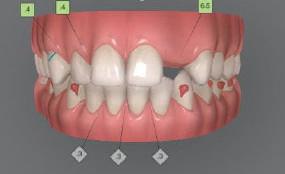

Dental Tribune Bulgarian Edition / октомври 2022 г.16 клиничен случай с алайнери Г орният латерален ре зец е вторият найчесто вродено липсващ зъб.1,2 Поради разполо жението му във видимата зона на усмивката лечение то на подобни случаи нала га мултидисциплинарен под ход, целящ отличен функцио нален и естетичен резултат. Налице са няколко лечебни мо далности, свързани с различ но разпределение на място то: първият вариант е орто донтско отваряне на място и възстановяване на липсва щия зъб с конструкция, под държана от съседните зъби3 или от имплант4, докато при втория подход разстоянията се затварят и премоларът заема мястото на канина.5 Изборът на лечебен подход трябва да бъде направен съв местно от зъболекар и паци ент въз основа на очакванията на последния и предвиди мостта на лечението. Множе ство фактори влияят върху това решение, като напри мер типа малоклузия, размера, формата и цвета на кучеш ките зъби6, оклузалните вза имоотношения (овърджет и овърбайт), лицевия профил, дължината на зъбната дъга и несъответствията в разме ра на зъбите.7 В настоящата публикация се разглежда случаят на жена в зряла възраст с вродена лип са на горен ляв латерален резец. Бяха приложени про зрачни алайнери за отваряне на място за единичен им плант и бяха постигна ти функционална оклузия и отлична естетика. ПРЕДСТАВЯНЕ НА СЛУЧАЯ Диагноза Пациентката бе на 32 годи ни, когато лечението започна, и първоначалното ѝ състоя ние бе следното (фиг. 1–3): липсващ горен ляв латерален резец; клас II, подклас I малоклузия; отклонение на горната сре динна линия вляво; Доклад на клиничен случай ЛЕЧЕНИЕ С АЛАЙНЕРИ НА ПАЦИЕНТ С АГЕНЕЗИЯ НА ЛАТЕРАЛЕН РЕЗЕЦ Д-р Iro Eleftheriadi и д-р Christodoulos Laspos, Гърция и Кипър Фиг. 1a–h Предоперативни лицеви и интраорални снимки. Фиг. 2a–e Дигитални модели преди началото на лечението. Фиг. 3 Панорамна снимка преди лечението. Фиг. 1a Фиг. 1d Фиг. 1f Фиг. 2a Фиг. 2d Фиг. 2b Фиг. 2e Фиг. 3 Фиг. 2c Фиг. 1b Фиг. 1e Фиг. 1g Фиг. 1h Фиг. 1c

Цели на лечението и лечебен план Целите на лечението бяха следните: нивелиране и подреждане на зъбите и в двете зъбни дъги; отваряне на пространство за липсващия латерален резец; коригиране на отношенията при канините и моларите до клас I; и корекция на отклонението на срединната линия. Лечебният план включваше: корекция на отношенията при кучешките зъби и мола рите до клас I с дистализира не на максилата; отваряне на пространство в областта на #22 за поставя не на единичен имплант; корекция на срединната ли ния; и създаване на място за раз ширяване на зъб #12 и апрок симална редукция в долната челюст с цел подобряване на несъответствието по Болтън и осигуряване на подобра оклузия. Изпълнение на лечебния план Този случай бе изпълнен със системата за алайнери Invisalign (Align Technology). Одобреният първоначален лечебен план предвиждаше 49 алайне ра с дистализиране на задни те горни зъби до клас I (прибли зително с около 3.5 мм; фиг. 5). За бъдещия имплант в областта на липсващия латерал бе планирано пространство от 6.5 мм, докато във фронталния сегмент на долната челюст бе предвидена апроксимална редук ция. В дясната страна бутон за ластици клас II бе поставен на зъб #47 вместо на зъб #46, за да не се увреди короната на импланта. Понеже пациентката жи вееше в чужбина,